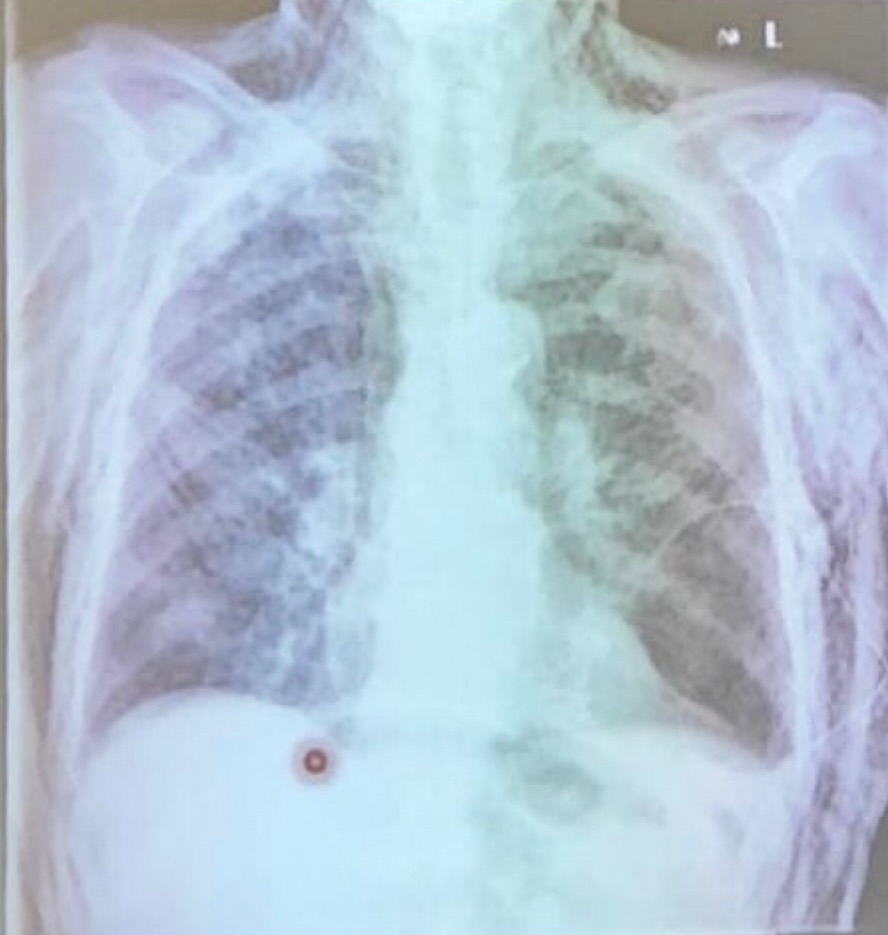

hidroneumotorax